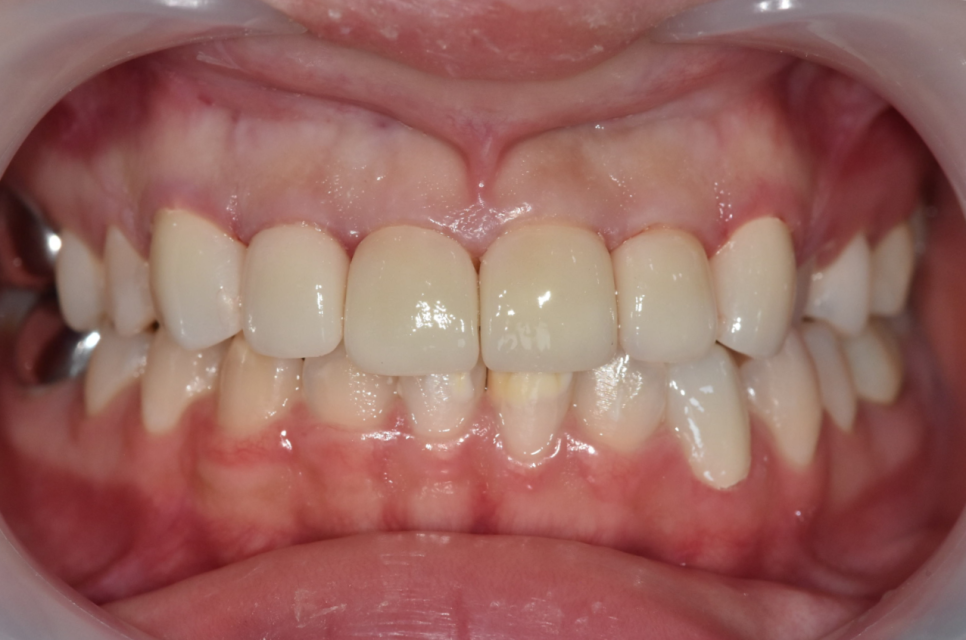

치료가 끝난 모습입니다.

250514

치료 전과 비교해 보았을 때 하얀 반점도 사라지고고, 치아도 가지런해졌습니다.

앞니를 살짝 길게 디자인해서 아래 앞니 반점도

자연스럽게 가려지는 상태입니다.